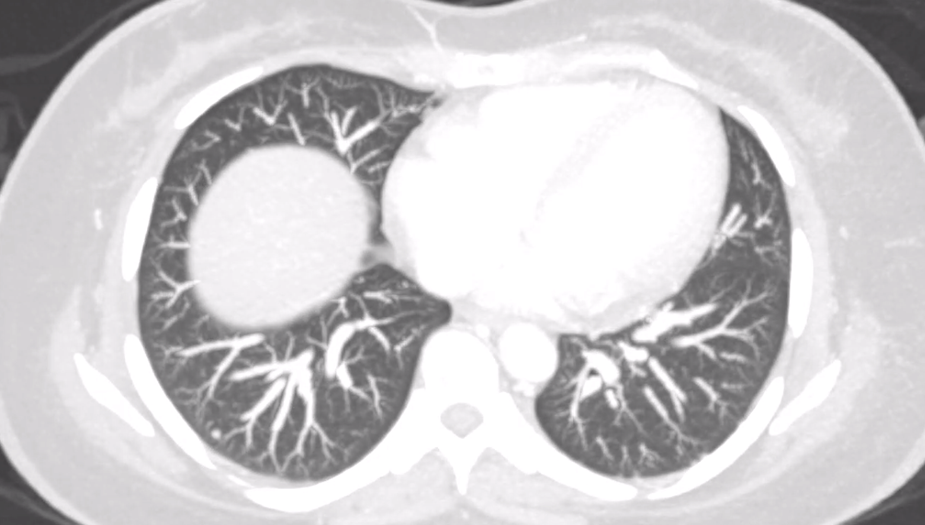

Computed tomography (CT) of the chest revealed multiple non-calcified subcentimeter pulmonary nodules (Figure 2). CT of the abdomen demonstrated a 7.5 × 10 × 10.9 cm lobulated, heterogeneously enhancing mass in the pancreatic body and tail (Figure 3A), invading the gastric fundus and encasing the splenic artery (Figure 3B), worrisome for malignancy.

Figure 2: Axial view of chest computed tomography with contrast revealing subcentimeter calcified pulmonary nodules.

Figure 3A Axial view from abdominal computed tomography with contrast that revealed a large, lobulated, heterogeneously-enhancing, mass arising from the pancreatic body and tail is identified measuring 7.5cm x 10cm x 10.9cm.

Figure 3B Axial view of abdominal computed tomography showing the associated encasement of the splenic artery.